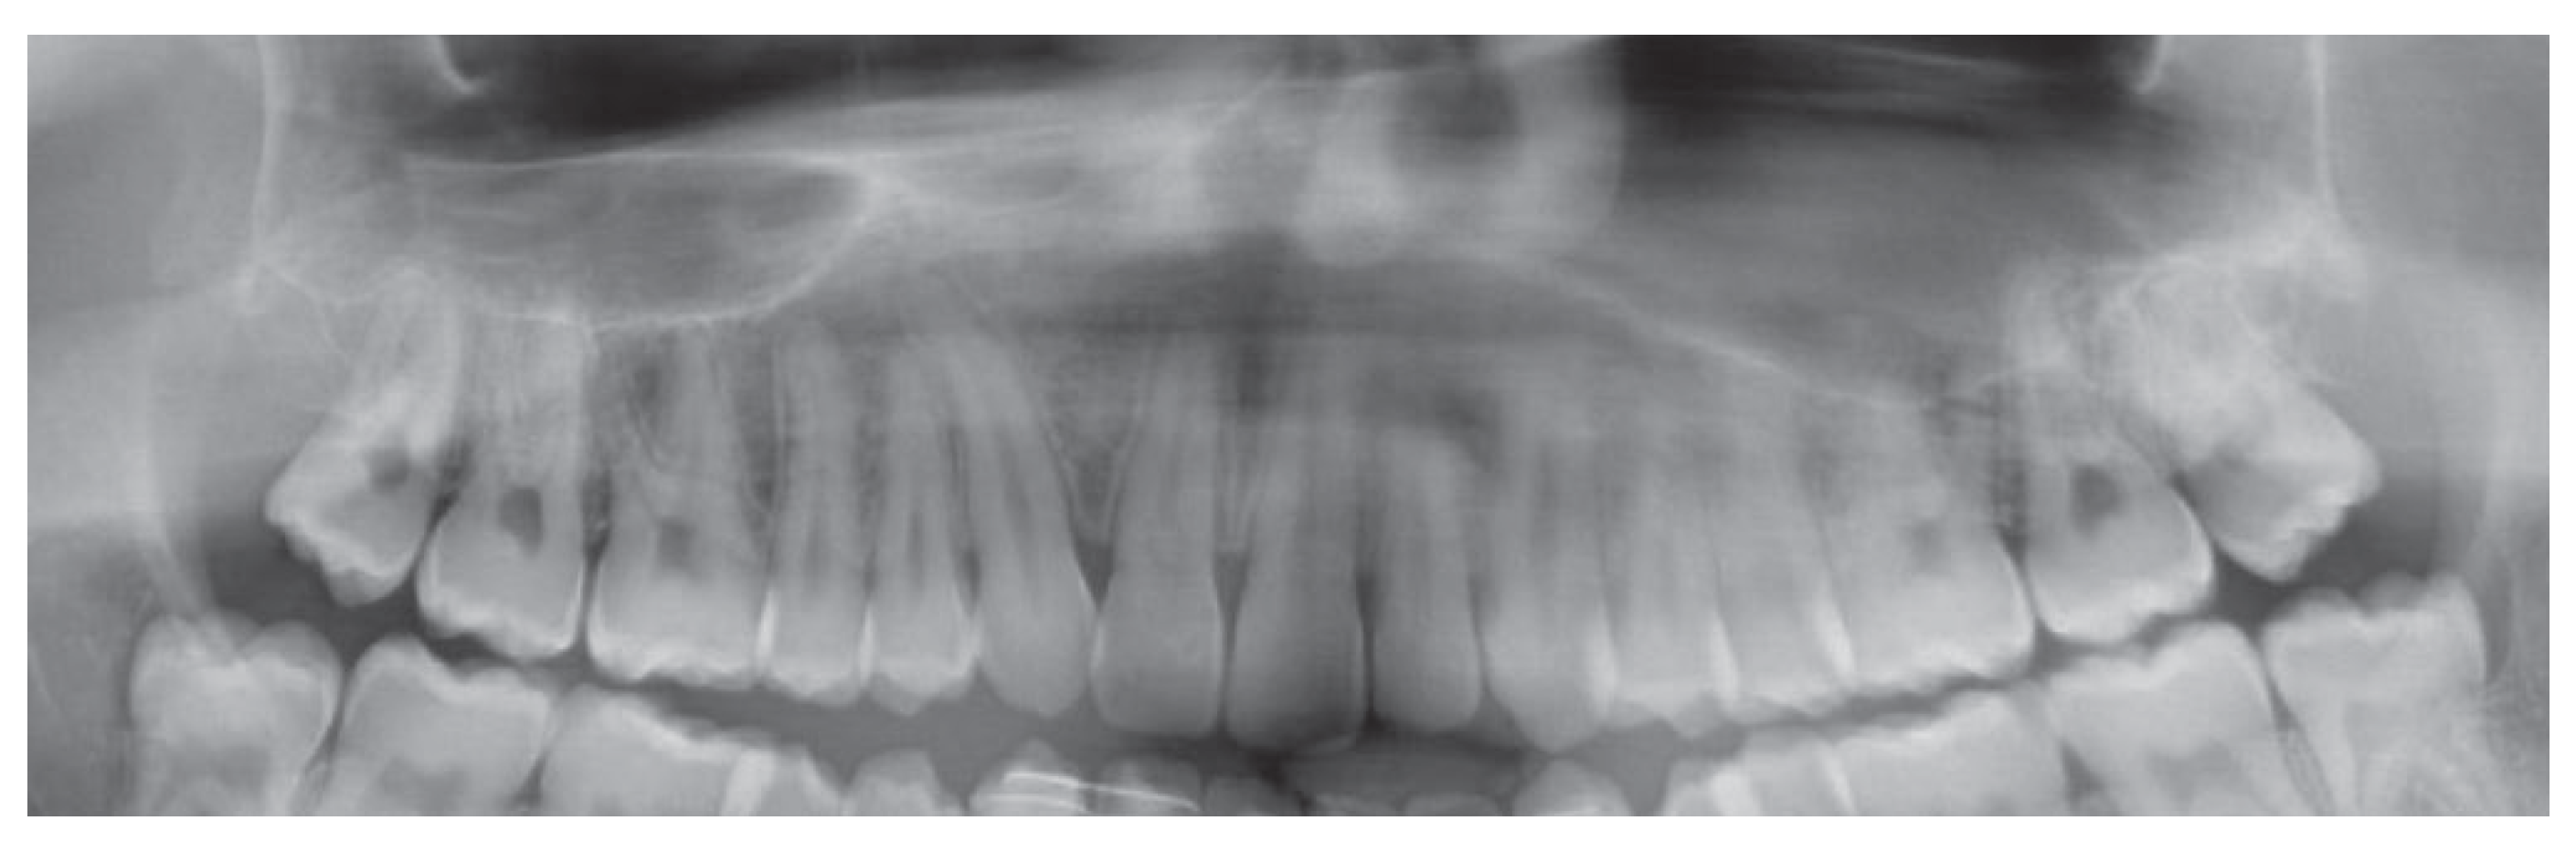

In all patients pre surgical records demonstrated adequate positions of the roots at the cutting sites, which allowed the surgical procedure (Figure 6).

Figure 6. same UCLP patient pre-surgical panoramic showing divergent roots of the central incisor and canine.